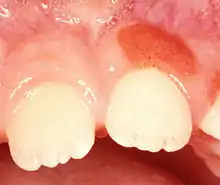

يظهر التهاب اللثة ذو الخلايا البلازمية كتضخم بسيط في اللثة الملتصقة وقد يمتد من اللثة الحفافية إلى اللثة الملتصقة.[8] وقد تمتزج بالتهاب اللثة الناجم عن اللويحة، أو قد لا تتضمن اللثة الحفافية. قد توجد كمنطقة حمراء منفردة ضمن اللثة الملتصقة (كما في الصورة). في بعض الحالات علاج التهاب اللثة أو التهاب دواعم السن الناجم عن اللويحة يعالج التهاب اللثة ذو الخلايا البلازمية الواقعة بضعة مليمترات من اللثة الحفافية المصابة بسبب اللويحة. في حالة وجود واحدة أو أكثر من الوحدات المصابة لا توجد أعراض يبلغ عنها المريض، ولذلك غالباً ما يتم اكتشافها من قبل طبيب الأسنان.[2] تكون اللثة حمراء هشة، مححببة، وفي بعض الأحيان تنزف بسهولة إذا أصيبت.[8] ويفقد التبقع اللثوي الطبيعي.[7] وعادة لا يوجد أي فقدان في روابط دواعم السن.[8] في بعض الحالات قد تتكون قرحة فم وإذا حدث ذلك يزداد الألم بمعاجين الأسنان أو أي طعام حار أو ساخن.[7] وقد تمتد الإصابة لتشمل الحنك.[7] التهاب الشفاة ذا الخلايا البلازمية يظهر كلويحة حمراء داكنة واضحة المعالم مغطاة بلمعة تشبه اللك.[5] وغالباً ما يتضمن الشفة السفلى.[3] الشفاه تظهر جافة ضامرة ومتشققة.[7] وقد يتواجد أحياناً التهاب الشفة الزاوي.[7] حين تتضمن الحالة اللسان يوجد تضخم حمامي مع أخاديد، ويفقد اللسان الطبقة التي تغطيه.[7]